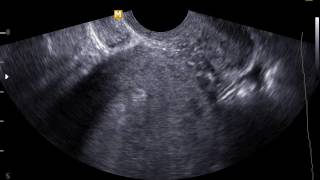

Если у вас есть подозрения на сотрясение головного мозга у грудного ребенка, обязательно обратитесь к врачу немедленно. Диагноз может быть поставлен после физического обследования и оценки симптомов. Иногда дополнительные исследования, такие как компьютерная томография (КТ) или магнитно-резонансная томография (МРТ), могут быть проведены для более точного выявления повреждений головного мозга.